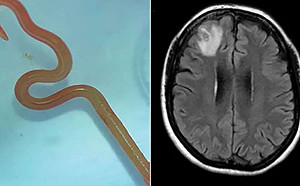

全球首例!澳洲婦人大腦取出8公分活的蛇蛔蟲